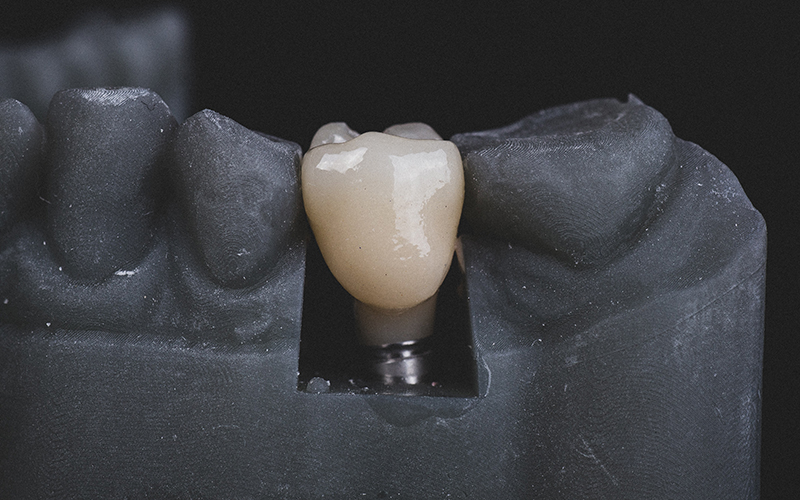

人工歯の装着

見た目・噛み合わせを考慮し、自然な仕上がりに調整します。